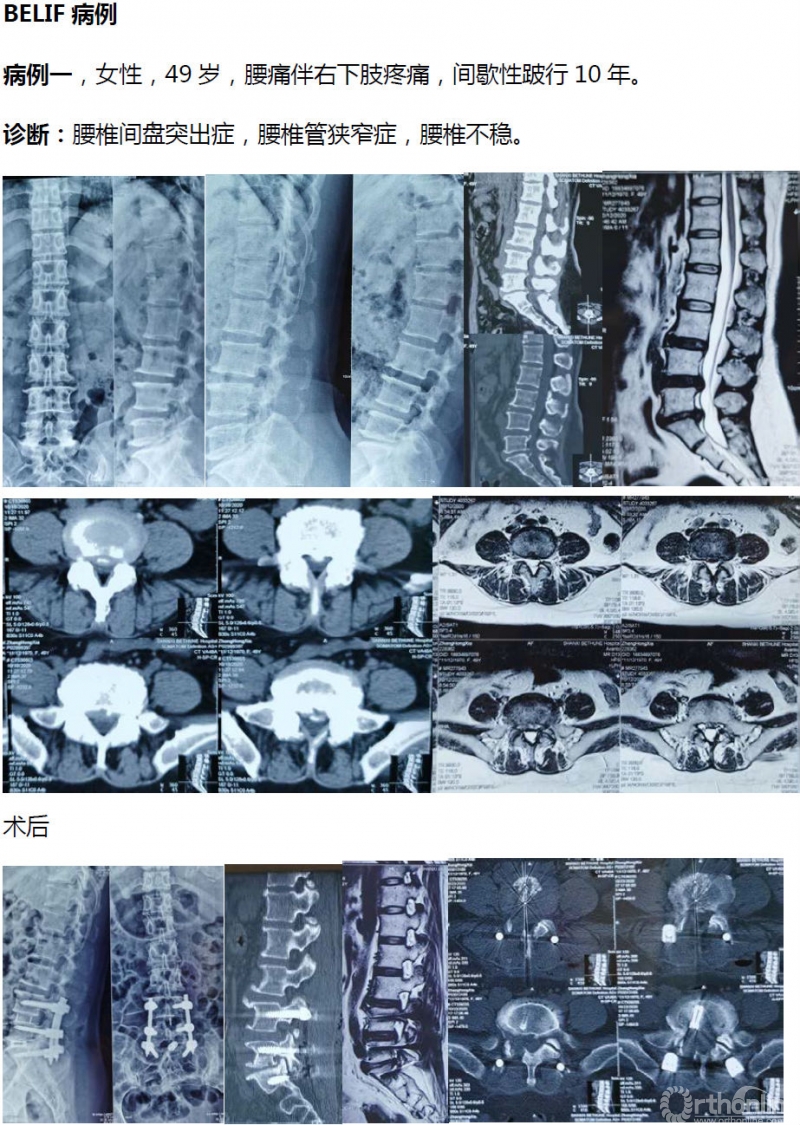

病例分享:(滑动查看)